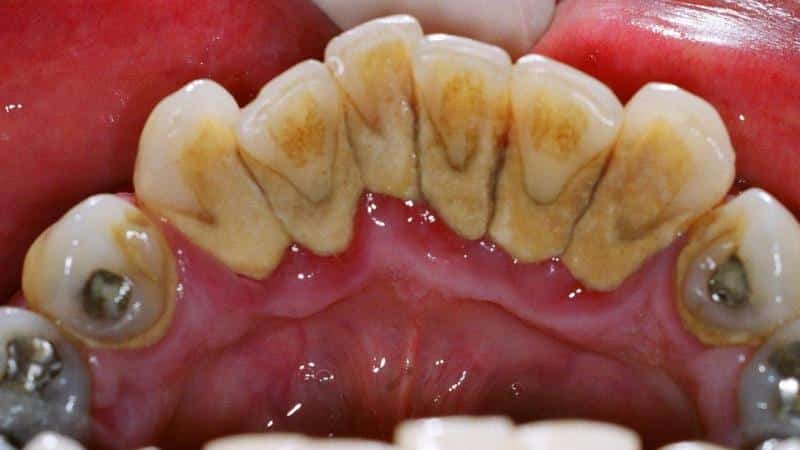

Строение зубного камня

Камень на зубах изначально представляет собой микробный налет, который прошел процесс минерализации и стал твердым, изменив цвет, консистенцию и иногда даже запах.

Стоматологи выделяют две основные формы зубного камня:

- Поддесневой — это известковые и микробные отложения, которые образуются в десневых карманах и остаются незаметными для обычного человека. Обычно их выявляют во время обследования пародонта специалистом.

- Наддесневой – это привычные темные участки, которые располагаются на жевательных зубах, резцах, молярах и других зубах, и их можно заметить при обычном осмотре ротовой полости в домашних условиях.

Зубные отложения состоят из неорганических компонентов (примерно 80%) и органических (до 20%). Неорганическая часть включает карбонат и фосфат кальция, соли, фтор, пигменты и другие химические элементы. Органическая составляющая состоит из лейкоцитов, белков, полисахаридов, нормальной и патогенной микрофлоры, отмерших клеток эпителия, остатков пищи и прочего.